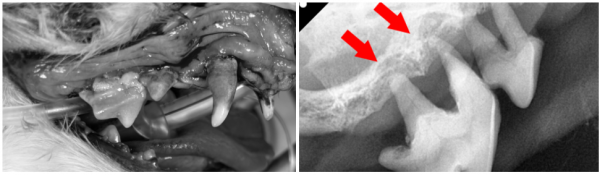

뭉이는 마취 후 치과 방사선 촬영을 진행했습니다.

치주염으로 인해 신경관이 좁아져 있었고

치조골 소실 및 치근단 농양이 확인되었습니다.